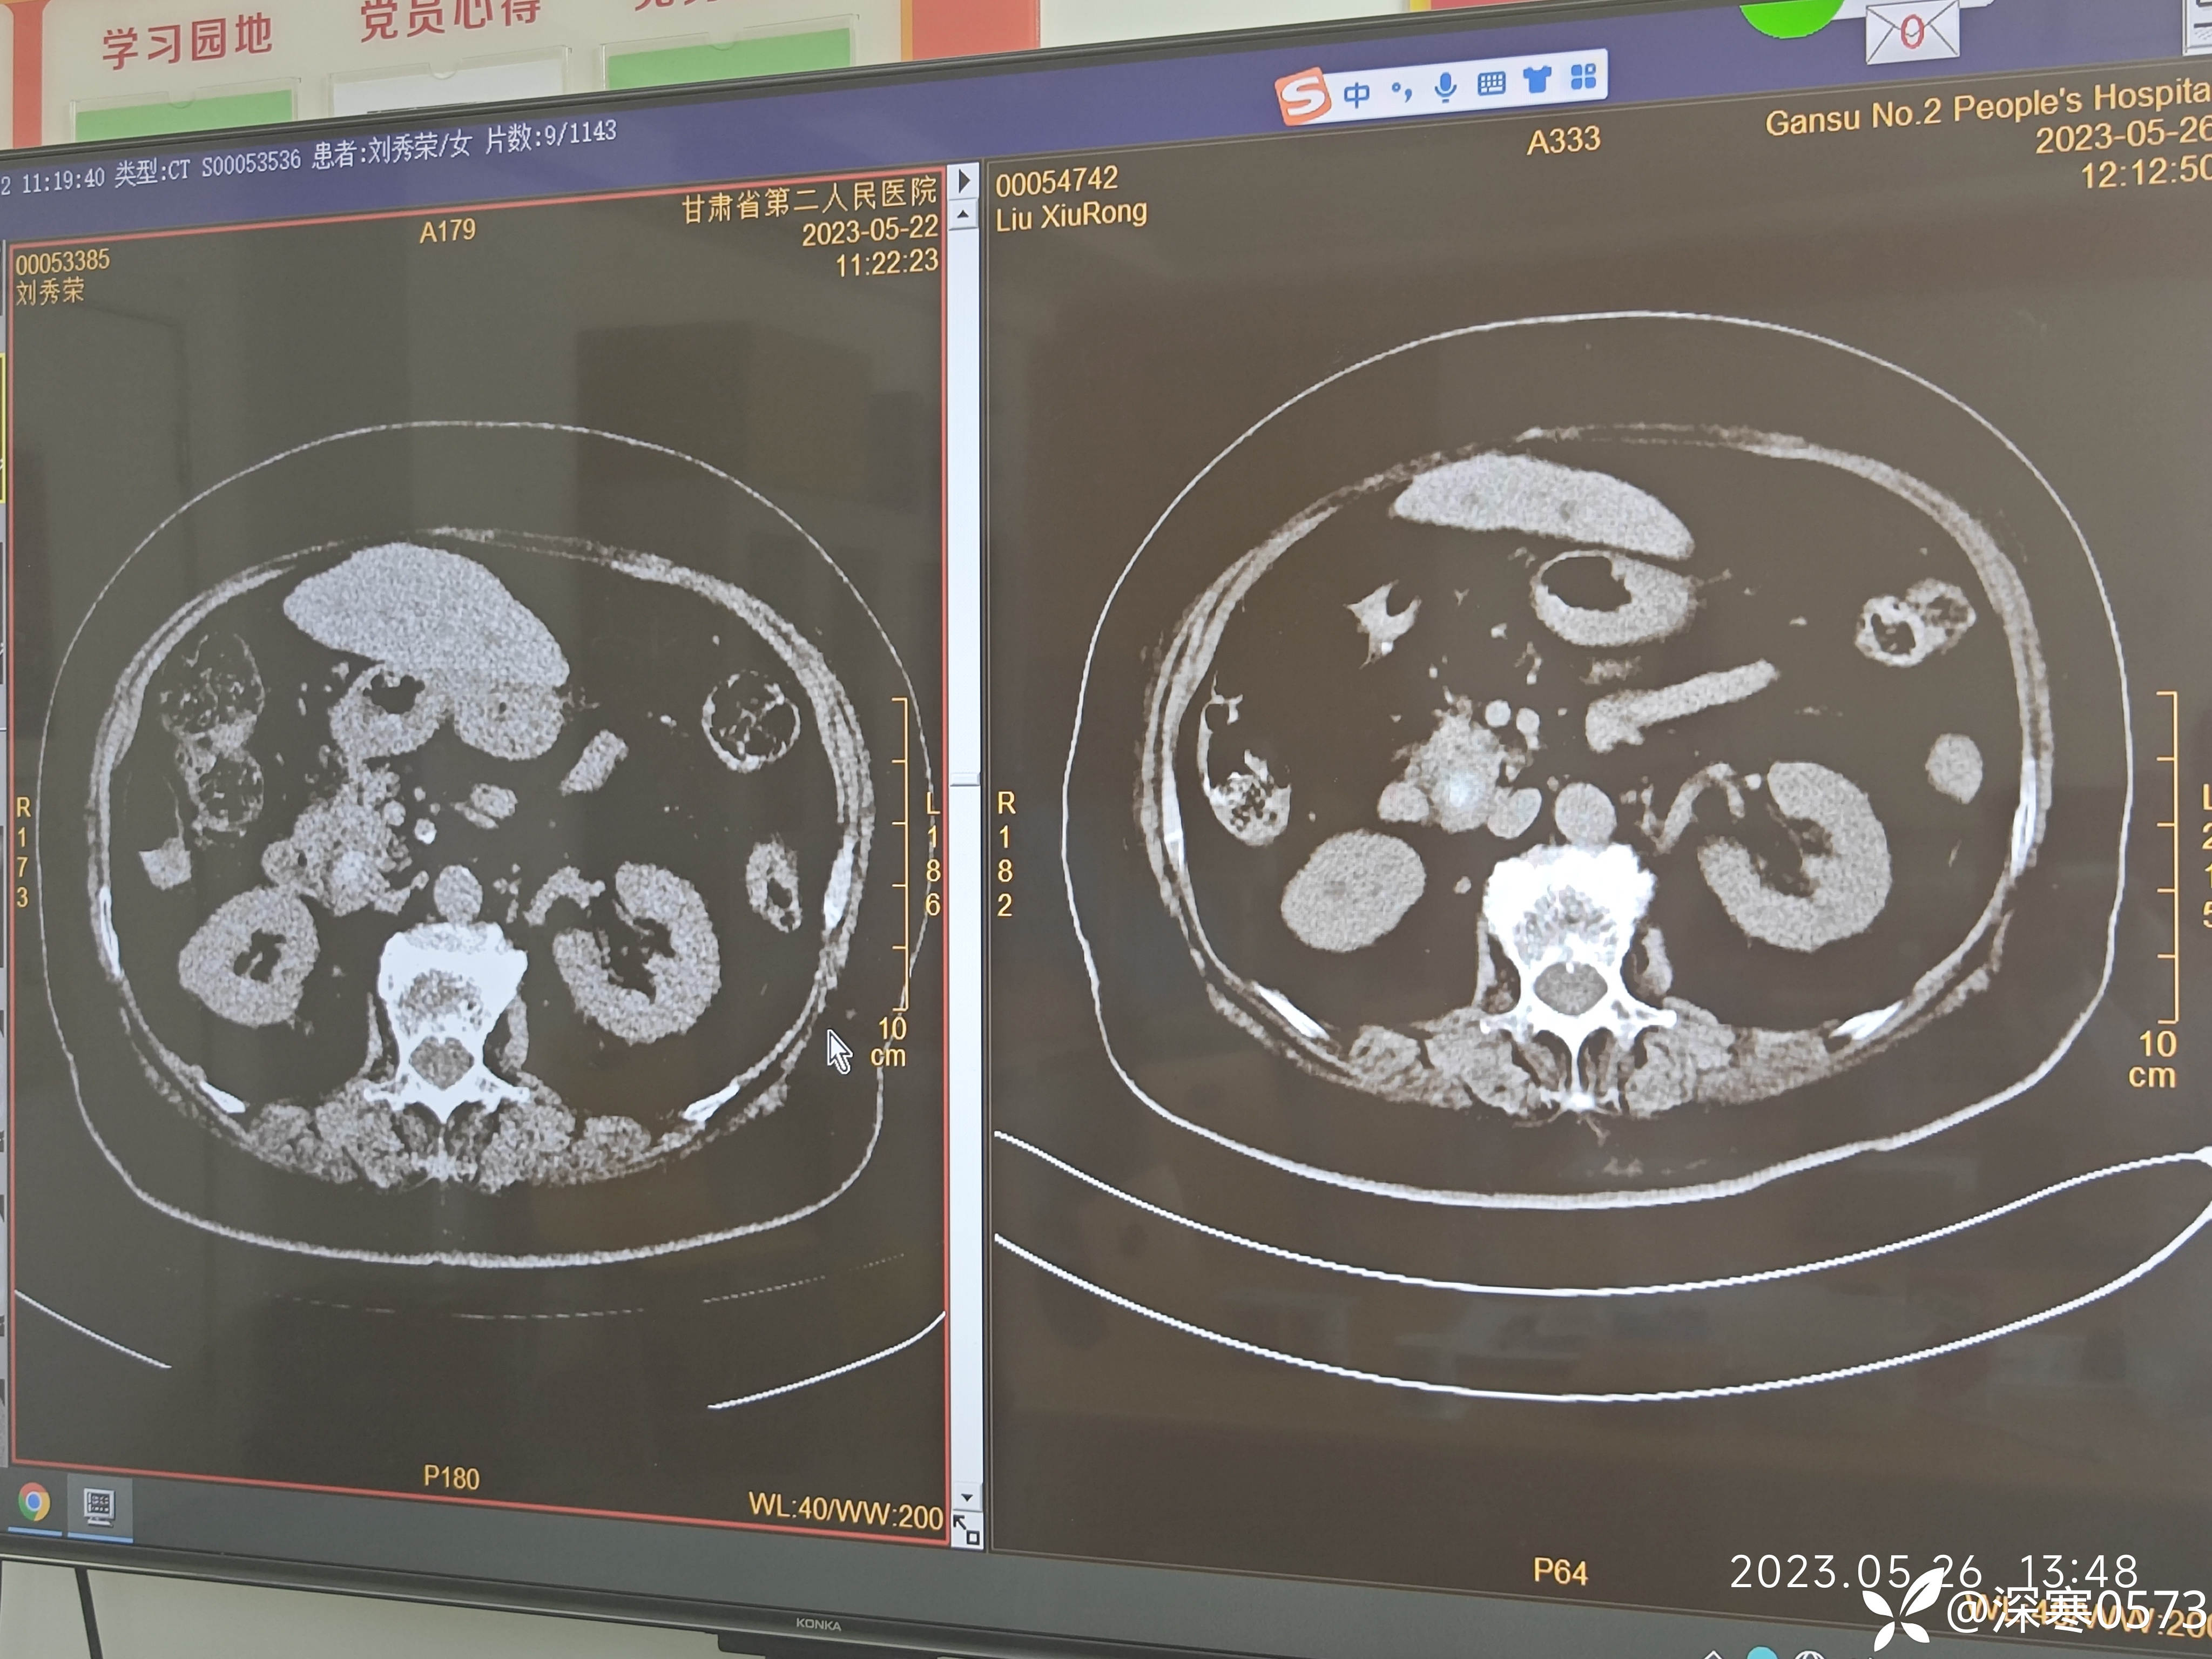

腹腔镜联合胆道镜经胆囊管取石:一镜到底,高清视频来了!

丁香医小白 推荐腹腔镜联合胆道镜经胆囊管取石操作难点包括:扩张胆囊管,无辅助进镜,镜下取石,探查肝内胆道(翻镜)等。

个人自2018年起行胆总管一期缝合,也曾经碰到过胆漏并发症,虽术后引流即可解决,患者并无特殊不适。但考虑经胆囊管取石更具优势且能避免胆漏并发症,故经多次尝试后形成成熟的操作流程和技巧,现已完成80余例经胆囊管取石取石,包括多枚结石,肝内胆管结石,较大结石钬激光等多种结石类型,术后患者均恢复良好,与胆囊切除术后恢复无异!